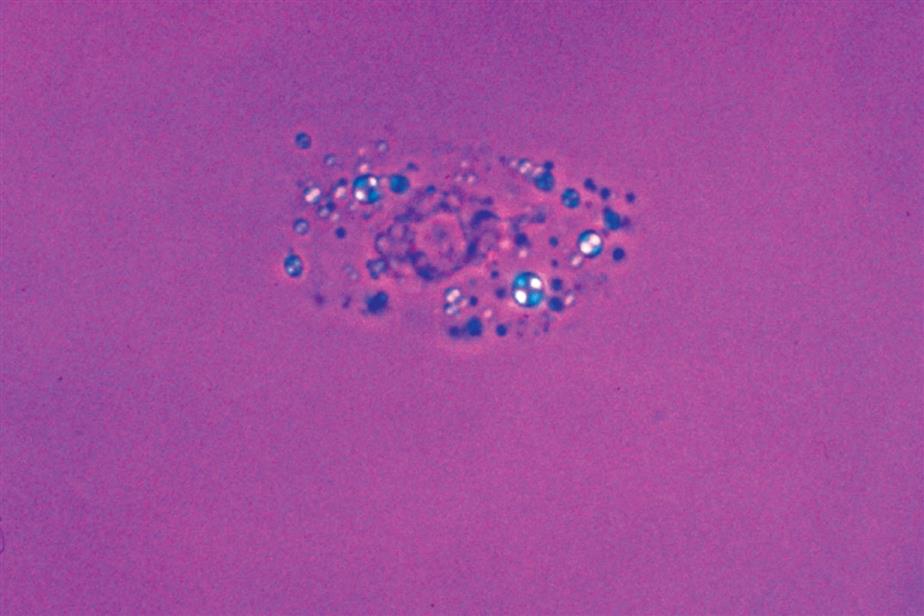

In addition to fusion of lobed nuclei (neutrophils), further evidence of cellular disintegration is seen in the formation of cytoplasmic blebs (Fig. 7.18). These blebs develop at the cell periphery on their outer membrane; they appear to be empty or may contain a few small granules. As these changes continue, the blebs can detach and become free floating in the urine or can remain within the cell, pushing the cytoplasm to one side and giving rise to large pale intracellular areas. Cytoplasmic blebs and vacuoles may also be observed with bacteriuria; the bacteria may be intracellular, extracellular, or both (Figs. 7.19 and 7.61).

Another degenerative change is the development of numerous finger-like or worm-like projections protruding from the cell surface (Fig. 7.20). These long filaments, termed myelin forms, result from the breakdown of the cell membrane. As WBCs die, additional vacuolization, rupturing, or pseudopod formation may be observed.